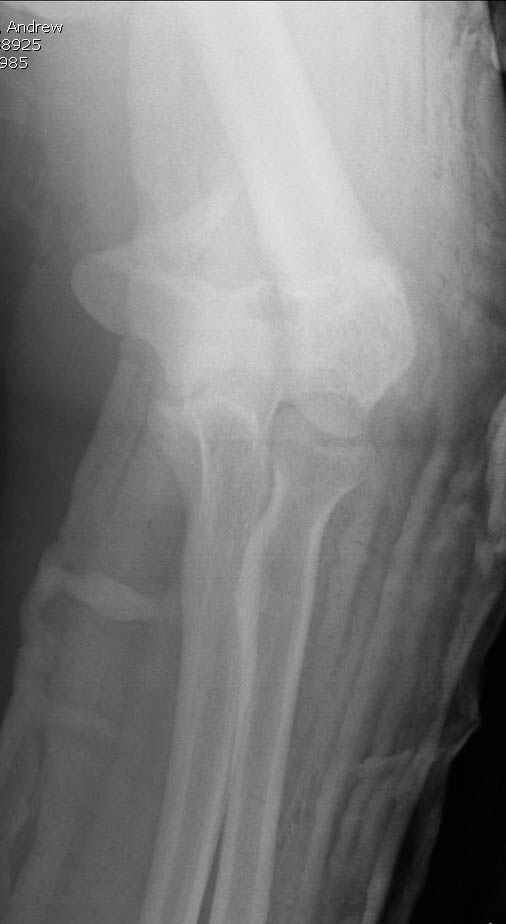

Alexander Artemiev 14 Сентябрь 2005, 16:19

Женщина 42 лет, операция через неделю после перелома.

Д-з - открытый перелом мыщелков со смещзением и локтевой кости

без смещения - падение с лошади.

До операции снимки не очень, тем более в гипсе.

Остеосинтез закрытый (если так можно выразиться), т.е. без

разрезов. Длительность операции - около 1,5 часа со студентом.

6 щелчков ЭОПом.